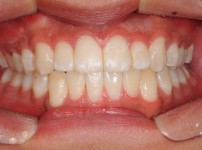

6

BEFORE

AFTER

클릭 해주세요.

전체교정

치아교정